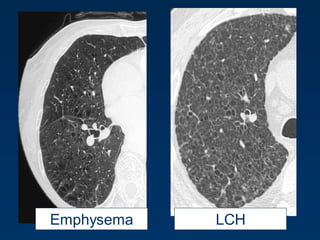

LCHEmphysema

Langerhans Cell Histiocytosis

HRCT Findings

Small peribronchiolar nodules (1-5mm)

Thin-walled cysts (< 1cm),

Bizarre and confluent

Ground glass opacities

Late signs: irreversible / parenchymal fibrosis

Honey comb lung, septal thickening,

bronchiectasis

1 year later

Peribronchiolar Nodules Cavitating nodules and cysts

Langerhans Cell Histiozytosis

Key Features

Upper lobe predominance

Combination of cysts and noduli

Characteristic stages

Increased Lung volume

Sparing of costophrenic angle

Emphysema

Emphysema typically presents as

areas of low attenuation without